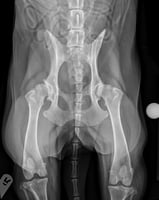

Diagnostic imaging for intestinal obstructions - which is best?

Imagine this clinical scenario: a client brings in their pet dog that is presenting with acute abdom...

11 min read